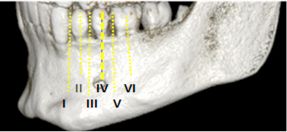

3D reconstruction was used to determine the location, shape and presence of accessory holes. To determine the location, the longitudinal axes of teeth were taken as reference as per Al Jasser & Nwoku's classification (21). Position 1: Mesial to first premolar; position 2: In line with first premolar; position 3: Between first and second premolars; position 4: In line with second premolar; position 5: Between second premolar and first molar, position 6: In line with first molar (Figure 3).

Figure 3: Location of mental foramen as per Al Jasser & Nwoku's classification

The most frequent location of the mental foramen was the longitudinal axis of the second premolar on both sides (position IV), followed by positions V, III, VI and II. No mental foramen was found in position I, neither significant differences compared to the contralateral side (p*0.764) (Table II).

3D reconstruction was used to determine the location, shape and presence of accessory holes. To determine the location, the longitudinal axes of teeth were taken as reference as per Al Jasser & Nwoku's classification (21). Position 1: Mesial to first premolar; position 2: In line with first premolar; position 3: Between first and second premolars; position 4: In line with second premolar; position 5: Between second premolar and first molar, position 6: In line with first molar (Figure 3).

Figure 3: Location of mental foramen as per Al Jasser & Nwoku's classification

The most frequent location of the mental foramen was the longitudinal axis of the second premolar on both sides (position IV), followed by positions V, III, VI and II. No mental foramen was found in position I, neither significant differences compared to the contralateral side (p*0.764) (Table II).